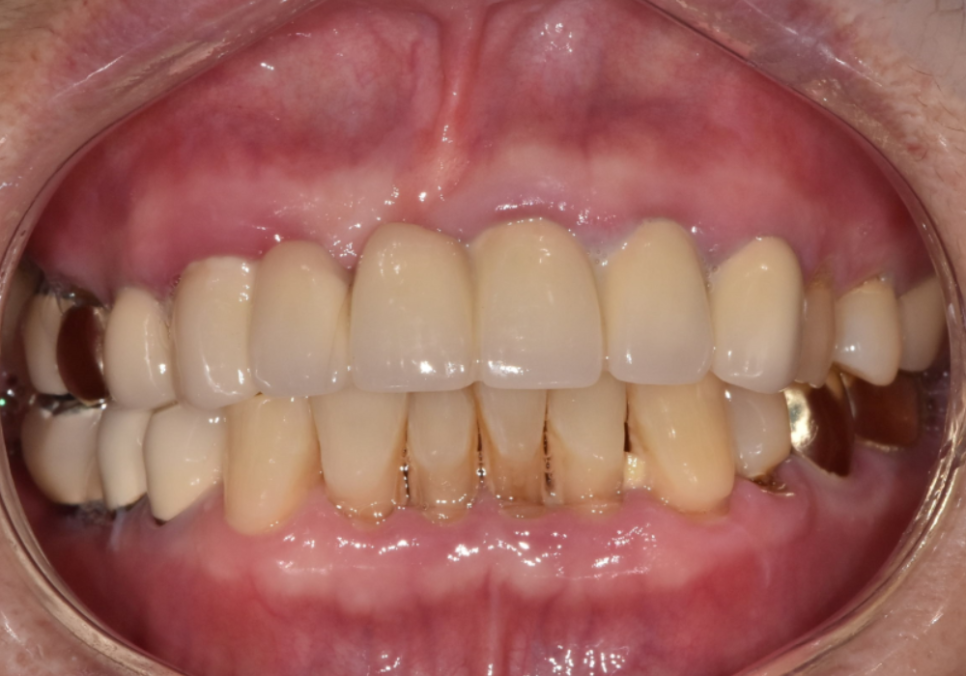

입안을 살펴보니 앞니 6개가 (#13~23)

브릿지로 연결된 상태였는데,

보철물과 잇몸 경계 사이로

고름이 계속 배어 나오고 있었어요.

240731

완성된 지르코니아 보철물을 보니

주변 치아와 아주 자연스럽게 어우러지는

만족스러운 결과가 나온 것 같습니다.^^